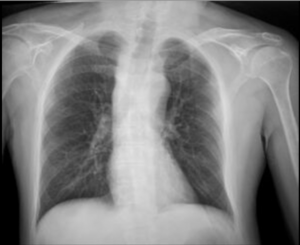

Caso 02